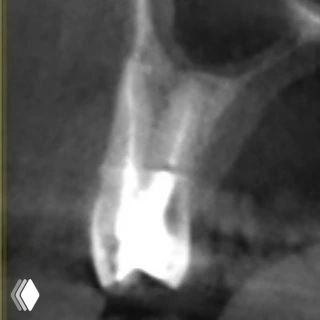

Распространенность: 1 премоляр вч - 3.2%, 2 премоляр вч - 0.4%

- проводить аккуратное расширение щёчных каналов, так как в области данных корней очень мало дентина (в моём случае расширение 25.04)